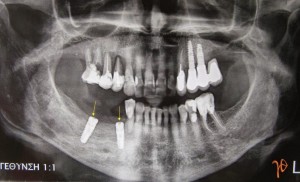

Τοποθετήθηκαν δύο εμφυτεύματα (3,8/13 και 4.5/13 Xive, Dentsply)(Εικόνα 4).

Δυόμιση μήνες μετά, κατά την διάρκεια της χειρουργικής αποκάλυψης, αφαιρέθηκε ο #44. Η όλη διαδικασία ήταν επιτυχής και ολοκληρώθηκε με την προσθετική αποκατάσταση της περιοχής(Εικόνα 5).